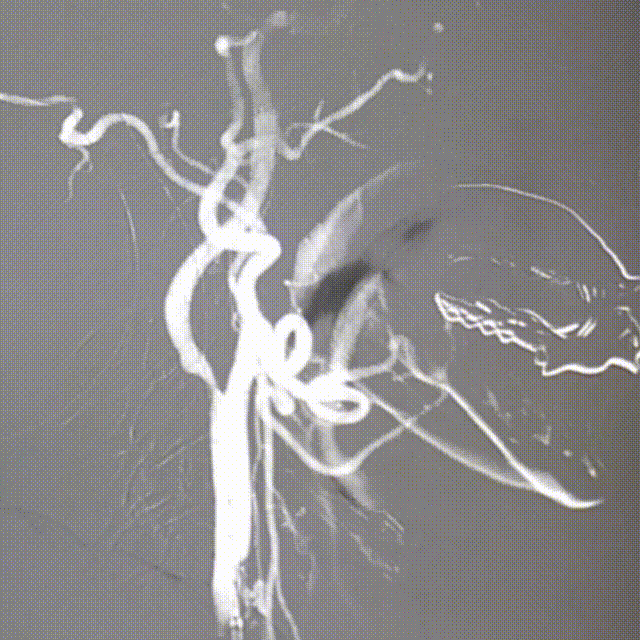

影像信息

右颈内造影

DSA提示:右侧颈内动脉起始部重度狭窄(狭窄率约70%)。

长鞘造影显示颈内动脉C1段无明显狭窄和夹层,远端显影良好。